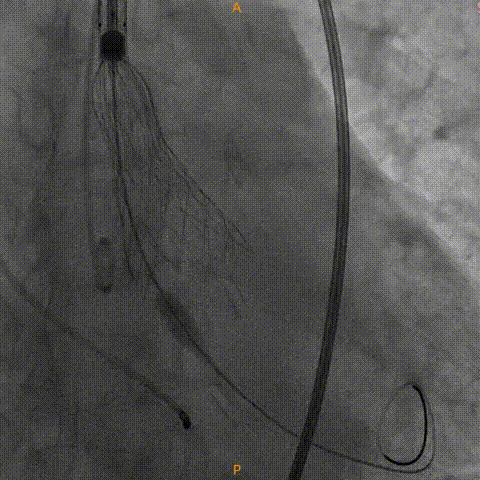

瓣膜零位定位释放

瓣膜完全释放

瓣膜膨胀不良进行球囊后扩